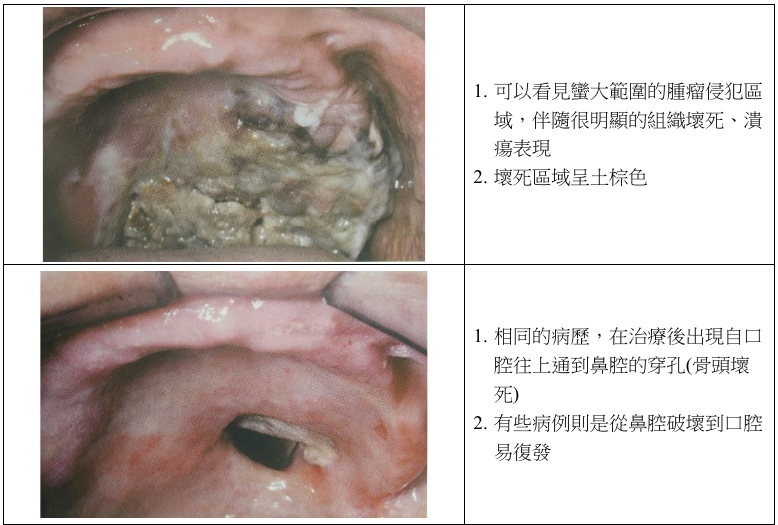

Extranodal NK/T Cell Lymphoma

- EBV related (100%)

- 淋巴結之外的 NK/T cell 所發展出來的

- 長在鼻中線

- 圍著血管長,侵犯血管 (尤其是動脈)

- 造成大區域缺血壞死

- 侵犯性強,化學治療不敏感 → 預後不佳,大部分病歷都在診斷後三年內過世